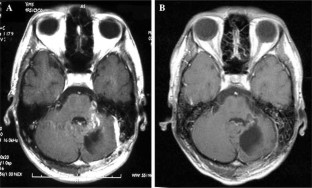

We report a case of a cerebellar tumor consisting of a mixed germ cell tumor (GCT) and a hemangioblastoma. A 22-year-old man presented with myoclonus and cerebellar ataxia. Magnetic resonance imaging showed a tumor mass in the left cerebellar hemisphere. The tumor was totally removed, and the histological diagnosis was an undetermined neoplasm. Ten months later, the patient returned with cerebellar hemorrhage at the site of the previous tumor. An emergency craniotomy was performed, and a tumor mass adjacent to the hematoma was resected. Microscopic examination revealed a mixed GCT consisting of a germinoma, choriocarcinoma, and mature teratomatous component. An area of hemangioblastoma was also found in the same tumor mass. A retrospective examination of the histological sample from the first operation indicated a germinoma. A primary GCT of the posterior fossa is very rare, and there are no other reports of the coexistence of a GCT and a hemangioblastoma. A metastatic GCT lesion of extracranial origin should be considered when the intracranial GCT is non-germinomatous and arises in an unusual site. The most probable hypothesis for the histogenesis of this case was a hemangioblastoma complicated by a “tumor-to-tumor” metastatic lesion of testicular GCT with “burnout” of the primary site.

Fig. 1